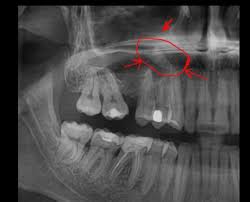

Рентген

При остром одонтогенном гайморите на рентгеновском снимке можно увидеть утолщение слизистой оболочки пазухи, уменьшение пневматизации и чёткий уровень жидкости — эти признаки указывают на выраженный воспалительный процесс. Также при обзорном снимке полости рта или прицельной рентгенографии заинтересованного зуба могут быть обнаружены признаки пульпита, периодонтита и нагноения кисты.

Проявлением длительного одонтогенного гайморита может быть незначительное уменьшение уровня заполнения воздушных полостей пазухи, при этом обнаруживаются незначительные воспалительные изменения в зубах и окружающих их тканях.